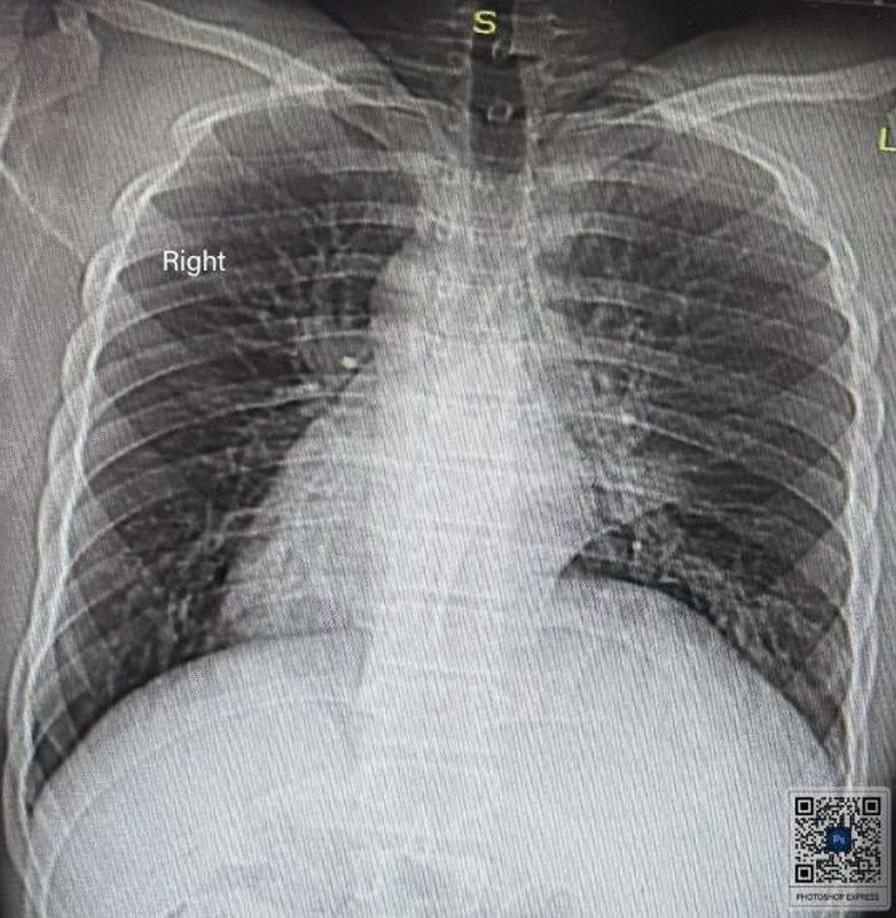

This case involved a 17-year-old Black African Semitic male patient who presented to our hospital with a complaint of intermittent productive cough, which started when he was 5 years old. He had a history of repeated treatment for lower respiratory tract infection and chronic sinusitis with frequent exacerbation. On examination, he had coarse crackles over the left posterior lower lung field. Heart sounds were appreciated on the right side. During imaging investigations, his chest X-ray posterior-anterior view showed dextrocardia and right side gastric shadow with left paracardiac bronchiectatic changes. A high-resolution chest computed tomography scan was suggestive of complete situs inversus. There were left lower lobe bronchiectatic changes. An electrocardiogram showed features of dextrocardia. Routine laboratory tests were within normal range. He was treated with thoracic physiotherapy, azithromycin 500 mg three times per week, and mucolytics, with no apparent exacerbations in the last 6 months.

该病例涉及一名17岁的黑非洲闪米特男性患者,他因间歇性咳痰前来我院就诊,这种情况始于他5岁时。他有下呼吸道感染和慢性鼻窦炎反复治疗史,且频繁加重。检查时,左后下肺野可闻及粗湿啰音。心脏听诊在右侧。影像学检查中,他的胸部后前位X线片显示右位心和右侧胃泡影,伴有左心旁支气管扩张改变。高分辨率胸部计算机断层扫描提示完全性内脏转位。有左下叶支气管扩张改变。心电图显示右位心特征。常规实验室检查在正常范围内。他接受了胸部物理治疗、每周三次500毫克阿奇霉素以及黏液溶解剂治疗,在过去6个月中没有明显加重。